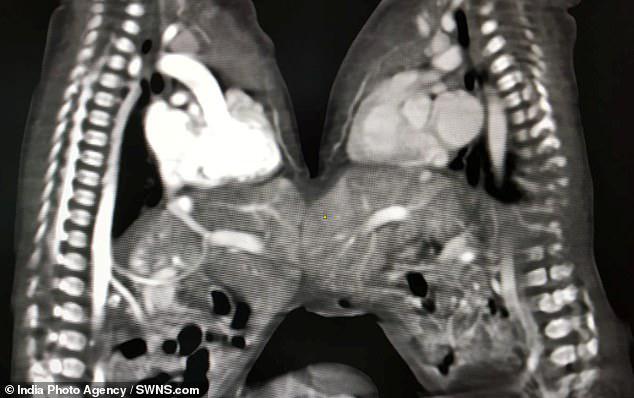

ئەنگىلىيە "كۈندىلىك پوچتا" گىزىتىنىڭ 11-دىكابىردىكى خەۋرىگە ئاساسلانغاندا، ھىندىستاندىكى بىر دوختۇرخانا، تۇغۇلغىلى ئەمدىلا ئۈچ كۈن بولغان ئۇلاشما تەنلىك بوۋاقلارغا ئايرىش ئوپراتىسىيى ئېلىپ بېرىپ، مۇۋەپپىقىيەتلىك ھالدا ئىككى بوۋاقنىڭ جېنىنى قۇتقۇزۇپ قالغان.

بۇ بىر جۈپ ئۇلاشما تەنلىك بوۋاقنىڭ بەدەن ئېغىرلىقى ئاران 7 قاداق(تەخمىنەن 6جىڭ 180 گىرامغا تەڭ) كىلىدىغان بولۇپ، ئۇلار ئاشقازان قىسمى تۇتاش ھالەتتە تۇغۇلغان؛ دوختۇرلارنىڭ تەۋسىيىسى ئاستىدا، ئۇلارغا قارىتا 5سائەتلىك ئايرىش ئوپراتسىيىسى ئېلىپ بېرىلغان بولۇپ، ئوپراتسىيە ئىنتايىن مۇۋەپپىقىيەتلىك بولغان؛ دوختۇرلار بوۋاقنىڭ ئاتا-ئانىسىغا خىزمەت ئىشلەپ، گەرچە ئوپراتسىيىنىڭ مۇۋەپپىقىيەتلىك بولۇش بولماسلىقىدىن ئەنسىرسىمۇ، بىراق ئوپراتسىيە قىلىشنىڭ ئۇلارنىڭ ئەڭ ياخشى تاللىشى ئىكەنلىكىنى چۈشەندۈرۈپ، ئۇلارنىڭ ئوپراتسىيە قىلىشقا قوشۇلۇشىنى قولغا كەلتۈرگەن.

بۇ قېتىملىق ئوپراتسىيە قىيىنلىق دەرىجىسى ئىنتايىن يۇقىرى "رىقابەت كۈچىگە ئىگە" ئوپراتسىيە بولۇپ، ئاخىرقى نەتىجە 5سائەتلىك ئوپراتسىيىنىڭ مۇۋەپپىقىيەتلىك بولغانلىقىنى ئىسپاتلىغان. دوختۇرلارنىڭ پەرەرز قىلىشىچە، بوۋاقلار كىلەر ھەپتىنىڭ ئاخىرلىرىدا ئۆيىگە قايتىپ كۈتۈنسە بولىدىكەن.

بۇ قېتىملىق ئوپراتسىيە 6-دىكابىر كۈنى ئېلىپ بېرىلغان بولۇپ، 5نەپەر تاشقى كىسەللىكلەر دوختۇرى، 10 نەپەر دوختۇر ۋە 15 نەپەر سېستىرادىن تەركىب تاپقان.